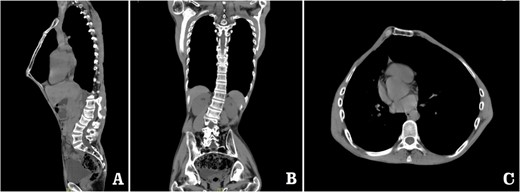

The patient was a 29-year-old male. He was found to have protrusive deformity on the anterior chest wall since childhood. The deformity was not serious in early years, but worsened after adolescence, with the lower part of the sternum protruding at an acute angle. At the age of 25, he developed right spontaneous pneumothorax and received surgical treatment at local hospital, but his thoracic deformity was not treated. As the deformity continued to worsen, which seriously affected the appearance of the chest wall, the patient was admitted to our hospital for surgery. Preoperative physical examination showed that the anterior chest wall was protrusive seriously, with a sharp tip protruding forward. The rib arches on both sides were slightly depressed (Fig. 1). Imaging examination showed that the anterior chest wall was protrusive, and the lower end of the sternum was at the forefront of the protrusion. His heart moved to the right, and the rib arches were slightly depressed (Figs 2–4). The operation was performed under general anesthesia. Two longitudinal incisions were made on both sides of the chest wall respectively. The incisions were located between the front axillary line and the median axillary line, with the length of ~5 cm. The chest wall muscles were dissected to expose the ribs in the incisions. Two tunnels were made on the highest plane of the protrusion, with interval of 3 cm. The tunnels were located in the deep layer of the chest wall muscles and bone structures. Two steel bars were inserted into the tunnels to flatten the front protrusion with their median parts, and then, both ends of the steel bars were fixed on the ribs at the lateral chest wall. The above operation was the main content of Wenlin procedure [1, 2, 5]. After this procedure was completed, the lower part of the chest wall showed obvious depression, especially in the middle of the rib arches. Then, Wung procedure was performed [6]. A third tunnel was made at the plane passing the midpoint of the rib arch, which passes through the bilateral thoracic cavity. The third steel bar was inserted into the tunnel. After the steel bar was rotated and fixed to the ribs, the depression was supported totally. The incisions were closed, and the operation was completed. The deformity of anterior chest wall disappeared completely after the operation (Fig. 5). The operation time was 75 min. The intraoperative bleeding volume was 40 ml. Postoperative X-ray examination showed that the bars position was normal (Fig. 6). He was discharged 7 days after operation. Follow up for 1 year showed satisfactory recovery. The steel bars were taken out 1 year after the operation, and the appearance of the thorax was normal and there was no recurrence (Fig. 7).

Preoperative 3D reconstruction pictures. (A) Left side view;and (B) right side view.